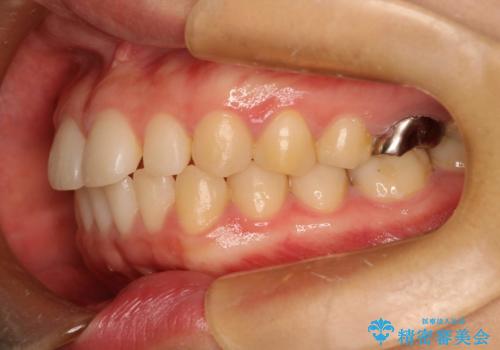

Invisalign インビザライン lite ライト 隙っ歯の改善

- 20代女性

- invisalign lite

- 6ヶ月

- マウスピース矯正による隙間の閉鎖を計画しました。

簡便な処置のため、ライトを選択しました。

かみ合わせが深くない空隙歯列は、最も簡単にその改善が見込まれます。